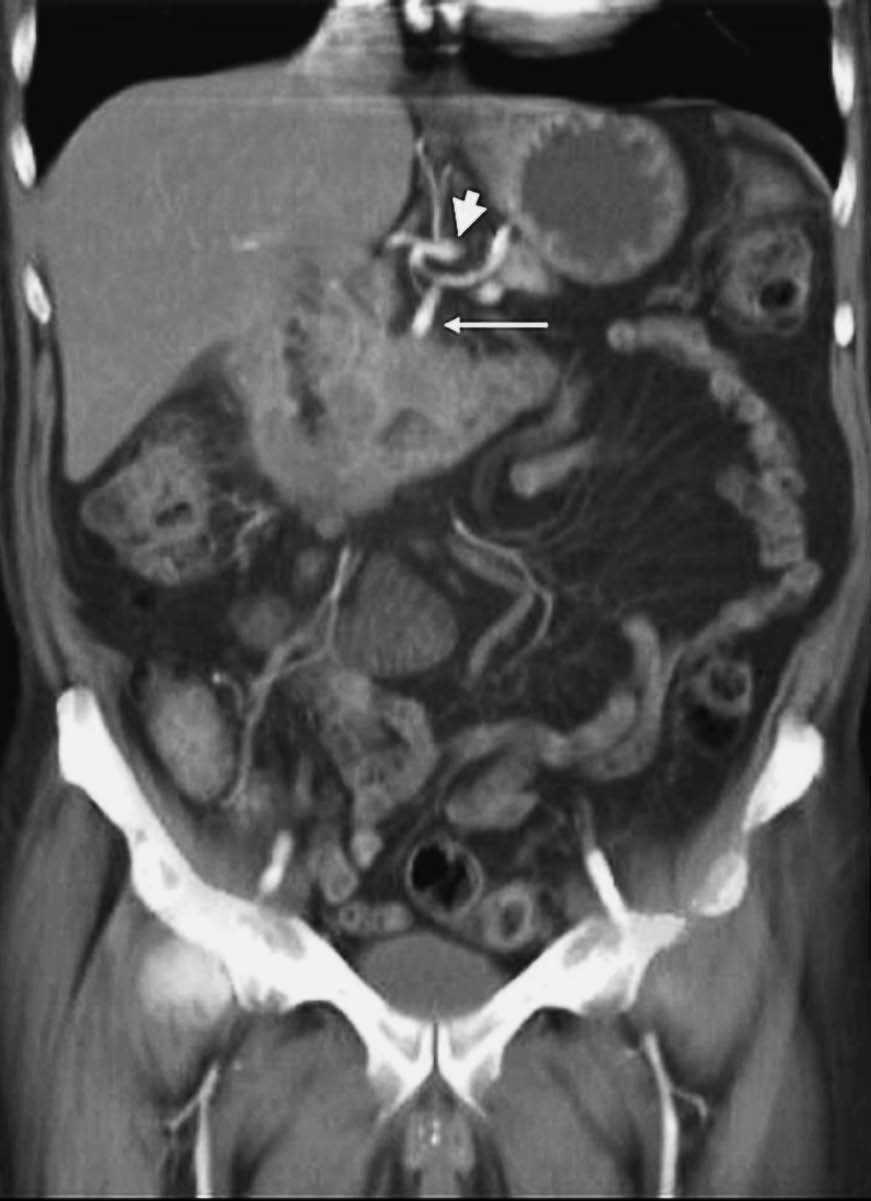

Fig. 11.--Reconstrucción coronal de una secuencia FSPGRE (fast spoiled gradient-echo) 3D potenciada en T1 en fase venosa portal tras la administración de contraste endovenoso. Reducción de calibre superior al 50% de la vena porta por un tumor de la cabeza pancreática.

El estudio dinámico volumétrico tridimensional con saturación grasa permite una precisa visualización de las estructuras vasculares arteriales y venosas peripancreáticas50,51, lo que posibilita la evaluación de la extensión vascular local (fig. 11). Hochwald et al52 revisan retrospectivamente los estudios de RM y de colangiopancreatografía por RM (CPRM) de 21 pacientes con sospecha de cáncer de páncreas para determinar su resecabilidad. La técnica detectó todas las lesiones y mostró un rendimiento diagnóstico para diferenciar entre lesiones pancreáticas malignas y benignas del 81%, y del 43% para predecir la afectación ganglionar. En cuanto a la predicción de la resecabilidad tumoral, los autores describen una sensibilidad de la técnica del 100%, especificidad del 83%, valor predictivo positivo del 94% y negativo del 100%. La precisión diagnóstica de la RM, incluyendo la CPRM fue del 95%. Los buenos resultados que presentan estos autores muy probablemente se deben a que evalúan la rentabilidad de la RM en 21 pacientes con masa pancreática, aunque sólo 16 de ellos tenían un adenocarcinoma ductal pancreático (10 fueron resecados, mientras que los 6 restantes fueron irresecables). Los datos se han calculado sobre 15 tumores resecables sobre los 21 que constituyen la serie.